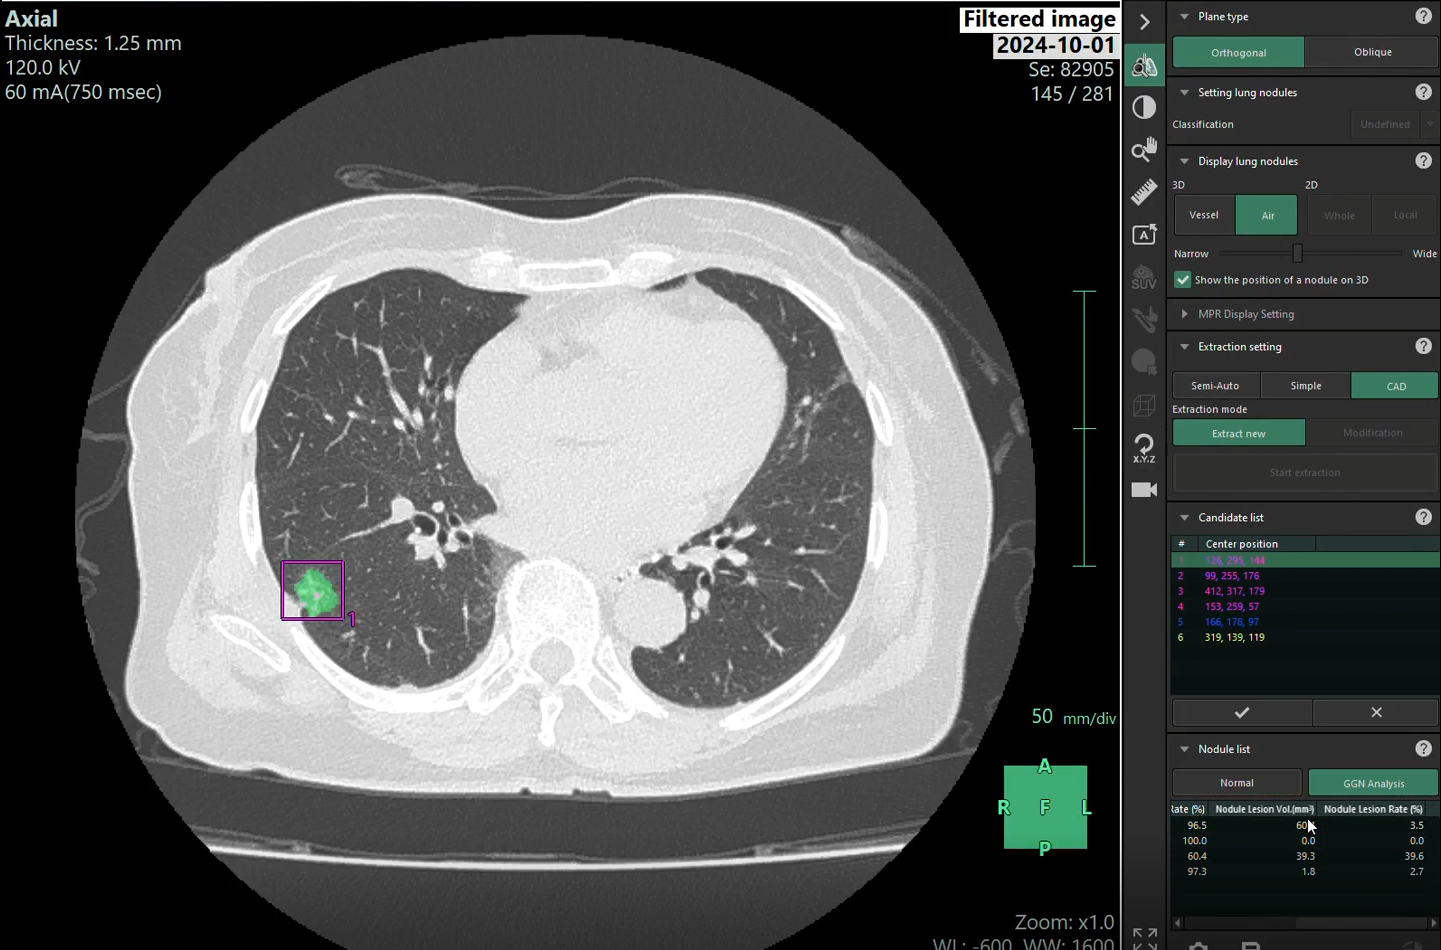

A lung cancer case detected and alerted early by AI. Photo: Nura

In another case, a woman in her 40s diagnosed with pneumonia at another facility and undergoing treatment for a month came to Nura for screening. A 10 mm lung lesion was discovered. The AI assessed the lesion as having irregular borders, unclear blood vessels, but a high cell density, with a solid nodule ratio of nearly 70%. Based on these suggestions and the doctor's clinical experience, Nura advised a biopsy, which confirmed stage one lung adenocarcinoma.